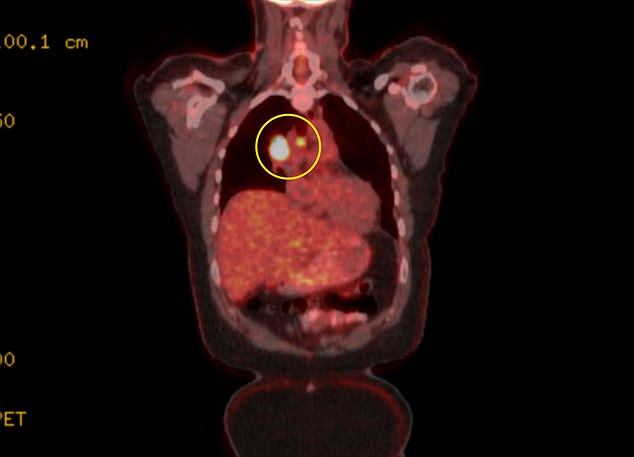

In the end, Lucas was unable to walk due to severe coughing, and after several months of fluctuating conditions, she was scheduled for a PET scan to obtain detailed medical imaging at the end of November.

Following several months of discussion, Lucas finally underwent a PET scan in November 2021.

In December 2021, Lucas was diagnosed with stage 3A lung cancer. The five-year survival rate stands at around 36 percent.

Stage 3A lung cancer is a form of non-small cell lung cancer (NSCLC) where the tumor has exceeded 5cm in size and has spread to lymph nodes in the chest area.

I saw three tumors on my X-ray in my right lung, each about the size of limes, and the cancer had spread to the central area, including the lymph nodes.